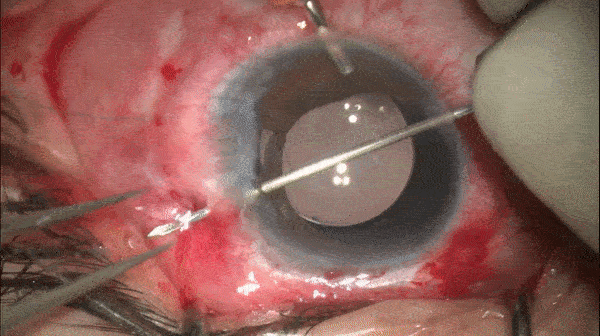

Step 12

截取离断虹膜、引入和引出缝线

采用27G针头,从虹膜根部离断的对侧(鼻侧)进针,进针处距角膜缘2.0mm,在眼内穿过已离断的虹膜组织,随后从离断侧巩膜穿出。

开睑器怎么用术说睛彩 | 金海鹰教授:使用8-0缝线的无巩膜瓣人工晶体固定手术_https://www.jmylbn.com_新闻资讯_第16张